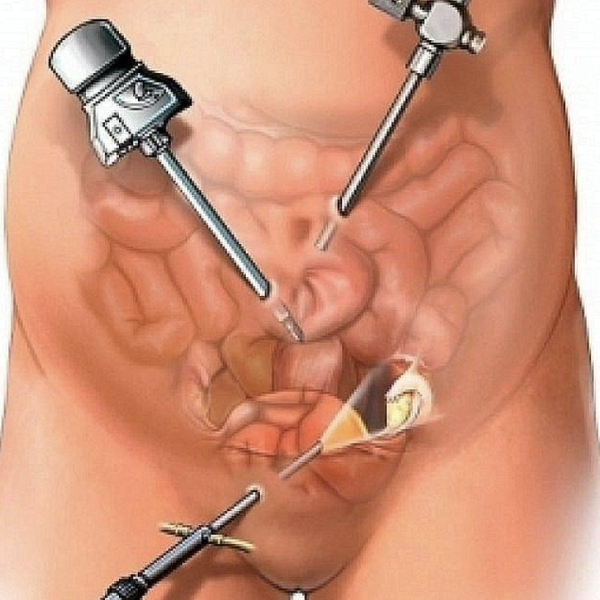

Tratamiento de apendicitis aguda, la diverticulitis, el prolapso rectal, el cáncer de colon